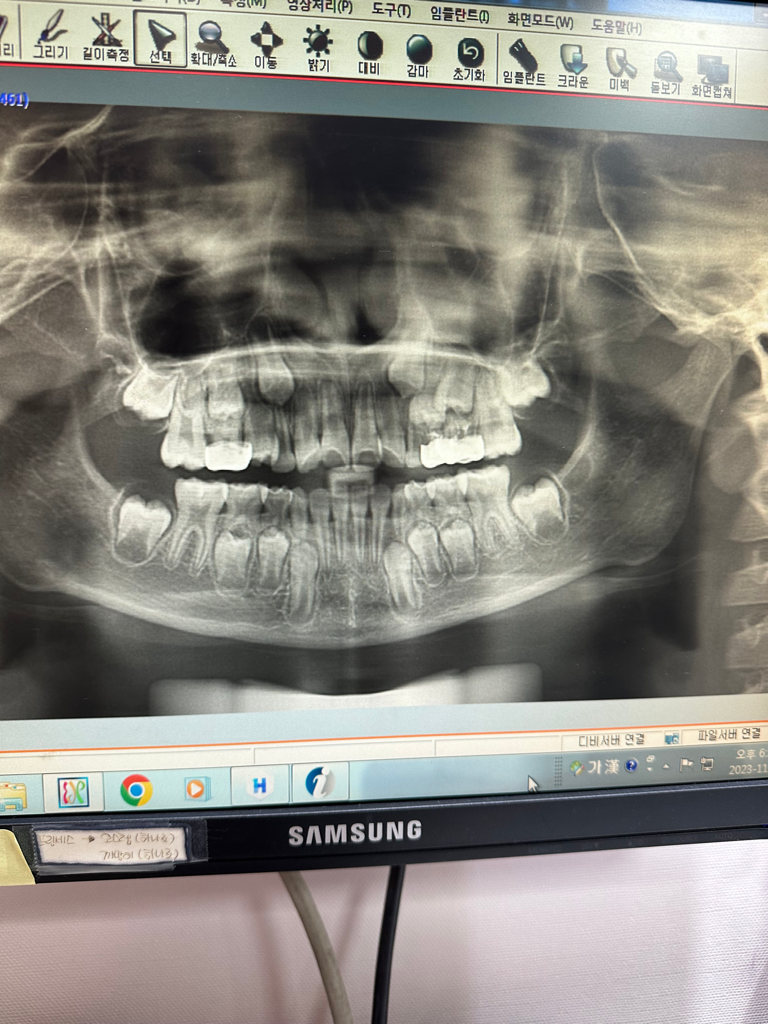

가볍게 검진하러 갔는데 왼쪽치아쪽 은니씌운부분에 염증이 튀어나와잇더라구요 고름이 차서 좀 크기가 커서 엑스레이를 찍으니 염증이 생각보다 많이 차있어서 치료를 받고 염증이 나아지지 않으면 발치까지 해야한다고 햇아요

두번의 염증치료후 세번째 염증치료하러 가니 다시 염증이 생걋다면서 파노라마 사진도 찍고 해보니 옆에 신경치료한 은니씌운이까지 번졌다면서 그쪽은 영구치가 많이

내려와 있으니 발치하는것도 좋은방법인걱 같다거 하시는거 일단 그 치아도 염증치료릉 해달라거해서 진행중입니다

파노라마 사진 첨부했습니다

• 1번 째 사진

엑스레이 상으로 보면 신경치료를 다시 하시거나 잇몸치료를 하셔야될것같습니다. 은니를 씌우면 관리가 쉽지 않아서 아이들도 치실을 사용해주시는게 좋습니다.